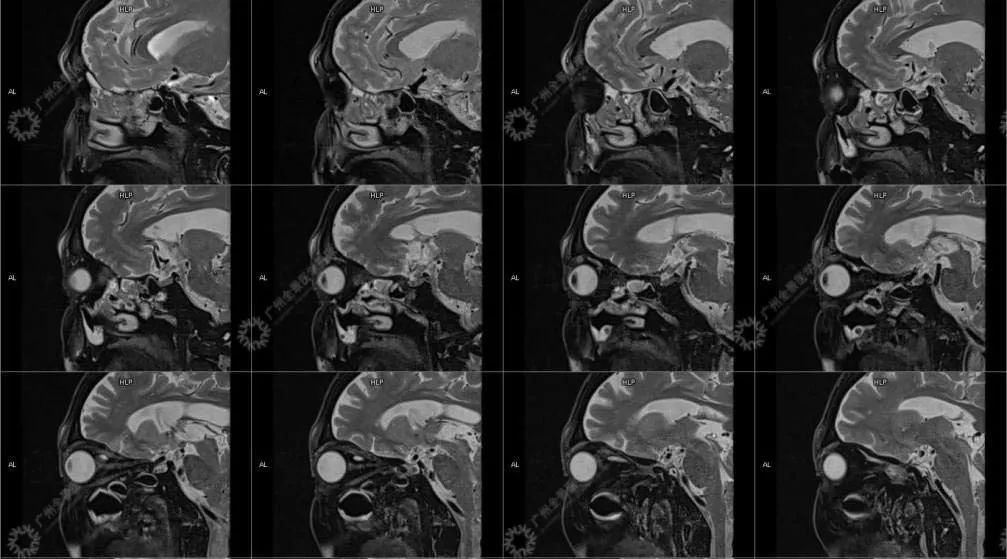

患者:男性, 71 岁

主诉:视力下降 2 年

现病史:双眼部隐痛、流泪,视力下降 2 年

结合影像及实验室检查,临床最终考虑 IgG4 相关性疾病。